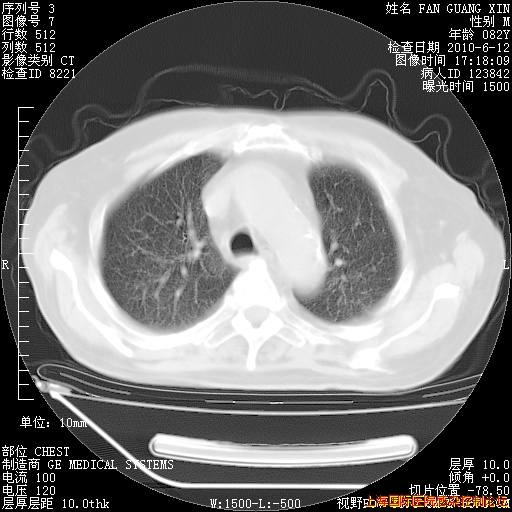

补发6月12日肺部CT肺窗

6月12日肺窗